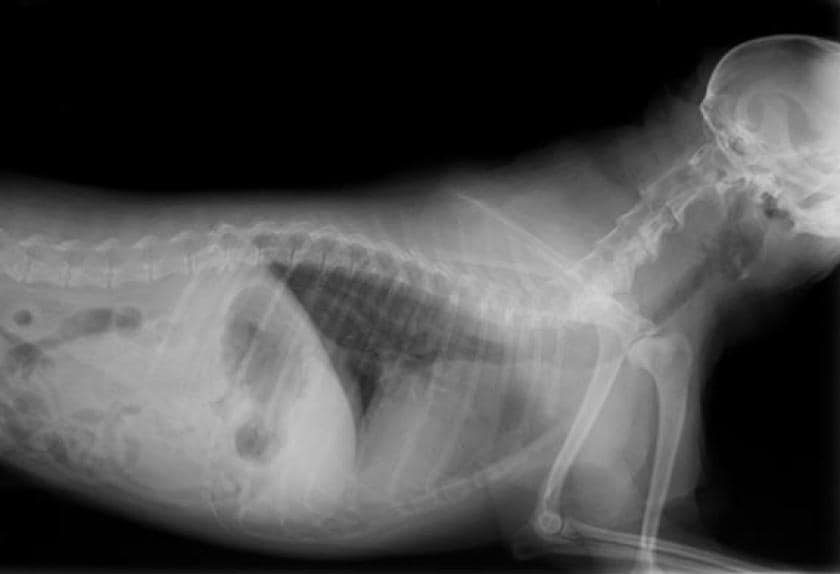

Secondary Lung Cancer In Dogs Life Expectancy : Liver Cancer In Dogs Symptoms Treatment And Life Expectancy Petmd - Primary lung cancer, which is quite rare and metastatic lung cancer, spread from other areas of the body.. Dogs who showed symptoms had a median survival of 8 months compared to 18 months in those without symptoms. Dogs with high grade (poorly differentiated) tumors with lymph node involvement have an average survival of three months, even with surgery. Our dog has cancer and we're not treating it. Primary lung cancer, or tumors originating in the lung, are relatively uncommon in dogs (less than 1% of all cancers in dogs), although the number. Lung metastases or metastatic cancer to the lung occurs when a cancer that originates in another area of the body, such as the breast or bladder, spreads to the lungs.

Scielo Brasil Pathological Features Of 78 Metastatic Or Multicentric Neoplasms Involving The Central Nervous System In Dogs Pathological Features Of 78 Metastatic Or Multicentric Neoplasms Involving The Central Nervous System In Dogs from minio.scielo.br And that is with chemotherapy! In this article we will help you understand the diagnosis of cancer in dogs. Only 1% of canine cancer diagnoses are lung cancer. On average, lung cancer in dogs will metastize in 2 to 10 months, depending on when the tumor is detected and what treatment options are available or the strength of the animal to fight the disease. Canine lung cancer life expectancy canine lung cancer is of 2 types: With pets living longer than ever, cancer has become a diagnosis that we see more commonly in older dogs. If the lymph nodes are involved or multiple tumors are found at the time of diagnosis, survival time is shortened to only 2 months. According to scientists, the average lifespan of those dogs is about 2 to 3 months.

Most dogs that have lung cancer are elderly, and the surgical approach is quite invasive. Canine lung cancer life expectancy canine lung cancer is of 2 types: Primary lung cancer, which begins in the lungs, is even rarer, but has a much lower canine life expectancy. If the lymph nodes are involved or multiple tumors are found at the time of diagnosis, survival time is shortened to only 2 months. If your dog is 8, and the average lifespan for his weight and breed is 10 years, and your veterinarian tells you that his survival time for his cancer is about 18 months to two years, and calls that a long time, he's right from a medical perspective. Most common symptoms anemia / coughing / lethargy / loud breathing / redness / swelling. Dogs with high grade (poorly differentiated) tumors with lymph node involvement have an average survival of three months, even with surgery. It hurts, and feels hopeless, but it's important to remember that it's not necessarily the end of the journey. In female dogs, mammary cancer also spreads to the lungs. The average survival is closer to 8 months for dogs with big tumors, and 2 months if there is metastasis. With pets living longer than ever, cancer has become a diagnosis that we see more commonly in older dogs. Dogs with lower grade tumor had a median survival of 22 months whereas dogs with higher grade tumor had a median survival of 6 months. Despite what research studies suggest, neither dog lived to their expected survival.

How We Helped A Dog With Metastatic Cancer Live 3 Years By Using Metronomic Chemotherapy Vlog 106 Youtube from i.ytimg.com The second type is metastatic lung cancer which is cancer that originates elsewhere in the body such as a leg bone, the mouth, or the thyroid gland, but has spread to the lung via the bloodstream. While there are treatments and methods for achieving remission or even curing cancer in dogs, each. Dogs treated for a single primary lung tumor which has not spread to the lymph nodes have an average survival time of about 12 months, however if the dog's lymph nodes also show signs of cancer, or if multiple tumors are found, life. However, if a lung tumor is found incidentally and your dog is not displaying any symptoms, they may have a life expectancy of up to 1 year. Lung metastases or metastatic cancer to the lung occurs when a cancer that originates in another area of the body, such as the breast or bladder, spreads to the lungs. If your dog already has evidence of cancer in other abdominal organs or in the lungs, the prognosis is grave and your dog may only have a few weeks left. Most dogs that have lung cancer are elderly, and the surgical approach is quite invasive. Primary lung cancer, which is quite rare and metastatic lung cancer, spread from other areas of the body.

Signs Your Dog Has Lung Cancer The Best Treatments Options For Your Dog Vlog 104 Youtube from i.ytimg.com Secondary lung cancer is when a cancer that started somewhere else in the body has spread to the lung. Unfortunately, some dogs diagnosed with lymphomas will not respond to treatment, and so it's important for owners to engage in open and empathetic conversations with vets. Most common symptoms anemia / coughing / lethargy / loud breathing / redness / swelling. Dogs live in the same environments we do and also eat many of the same foods we do. And that is with chemotherapy! A dog with a single primary lung tumor that has not spread to the lymph nodes has the longest average survival time (an average of 12 months); Your dog's tumor probably originated in his bones as osteosarcoma, in his mouth as oral melanoma, or in the blood vessels as hemangiosarcoma. For dogs with small, low grade (well differentiated) tumors without lymph node involvement, the average survival time is 16 months or longer with surgery alone.